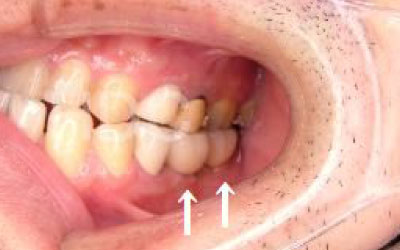

2 歯が傾いてくる、落ちてくる

歯はお互いに支え合ってバランスを保っています。つまり、歯が抜けるとその支えがなくなり、抜けた部分の隣の歯が傾いたり、上の歯が下にずれてくることがあります。

少しの位置ズレであれば、噛み合わせの調整や小さな詰め物で対応できます。

しかし、抜けてから数年経って歯が大きく傾いてしまった場合は、歯並びの矯正を行うか、歯を大きく削ってかぶせ物をする必要があります。